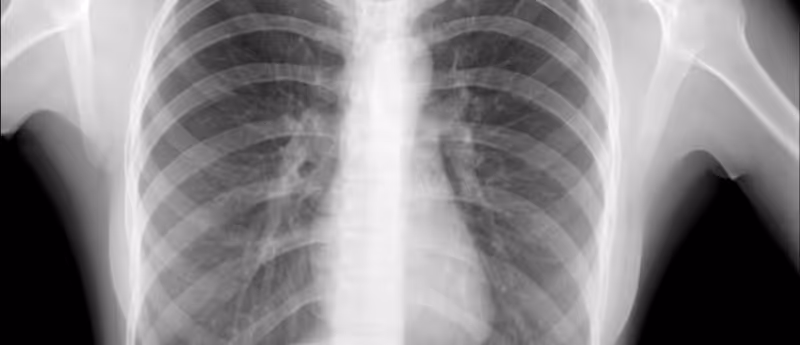

Bering Limited (London, UK) has just achieved a major milestone in medical diagnostics, with the US FDA granting 510(k) clearance for its innovative AI-driven chest x-ray (CXR) triage solution: ‘BraveCX’. This approval brings Bering’s advanced AI solution to the commercial market, reaching medical professionals and healthcare institutions across the US. BraveCX is a radiological computer-assisted triage and notification software specifically designed for analyzing CXR images of adults 18 years and above. The software efficiently identifies pre-specified inferred clinical findings, enabling immediate triaging and prioritization of emergency cases, including conditions like pleural effusion and pneumothorax, identified immediately after examination. By offering a valuable "second opinion" to physicians, BraveCX significantly diminishes the time-to-diagnosis for urgent cases. The foundation of this product is deep-rooted in a vast dataset comprising over 1,000,000 CXRs gathered from diverse clinical settings. BraveCX was further refined through the meticulous labeling of over 50,000 CXRs by board-certified radiologists. And why exactly has this product been the focus of FDA special treatment? Well, BraveCX has outstanding performance metrics, boasting 95%-97% specificity and Receiver Operating Characteristic (ROC) Area Under the Curve (AUC) scores (measures of accuracy for diagnostic tests) of 0.96 and 0.98 for pleural effusion and pneumothorax, respectively. With the much sought-after FDA clearance now in hand, Bering is poised to expand its market presence in the US. The company offers a versatile deployment model, allowing the utilization of BraveCX through on-premises installations, cloud-based services, or integration with existing CXR hardware systems. Through strategic collaborations with both new and established partners, Bering is positioned to swiftly introduce this revolutionary diagnostic tool to a broader audience. This market approval marks a significant milestone in the intersection of AI and healthcare, paving the way for enhanced diagnostic capabilities and improved patient outcomes. Ignat Drozdov, the CEO and founder of Bering, expressed his enthusiasm, remarking, “after over three years of research and collaboration with clinical teams, it’s so exciting to see BraveCX emerge as a state-of-the-art tool that has actually ‘listened to the end user’. FDA clearance means BraveCX prioritizes patient safety, whilst still delivering the most advanced Risk Stratification algorithms where they are needed the most.”